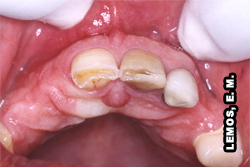

Aspecto clínico do dente 24, com dor provocada quando mastiga e com variações térmicas: quente e frio   Aspecto radiográfico do dente 24   Após remoção da cárie e restauração, houve exposição pulpar dos cornos vestibular e palatino. Obs.: este procedimento deveria ser feito com  isolamento absoluto

Preparos Protéticos

Para conseguir-se obter retenção e estabilidade da prótese necessita-se remover quantidade significativa de dentina. Devido aos estímulos térmicos gerados pelo atrito da broca contra o dente, instala-se uma reação de inflamação pulpar cuja reversibilidade depende de múltiplos fatores, tais como, idade do paciente, estado da saúde pulpar no momento do preparo, espessura de dentina remanescente, intensidade dos estímulos. Todos estes fatores devem ser observados para traçar-se o prognóstico da saúde pulpar e optar pela realização ou não do tratamento endodôntico previamente ao preparo cavitário.

Aspecto clínico do dente 11 e 21. Com relação ao dente 11, encontra-se com a polpa sã, apenas indicou-se a pulpectomia por razões da reabilitação protética   Aspecto clínico do dente 11 e 21, o paciente não relata nenhum sinal e sintoma com relação à dor   Aspecto radiográfico do dente 11 e 21